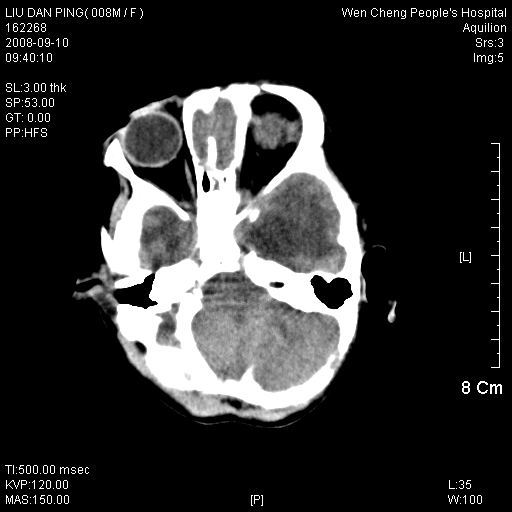

以下是引用卜一在2008-9-10 16:21:00的发言:[br]髓母细胞瘤伴梗阻性脑积水!支持![br]髓母细胞瘤特点:—般直径大于3.5cm,位于后颅凹中线之小脑蚓部。累及上蚓部的肿瘤延伸到小脑幕切迹之上,ct平扫肿瘤多呈均匀一致的高或等密度病灶,增强检查呈均匀一致的强化。病灶中有小坏死时,平扫亦可呈不均匀之混杂密度,注药后有增强。[br]

以下是引用zjzjr在2008-9-10 15:09:00的发言:[br]髓母细胞瘤伴梗阻性脑积水.